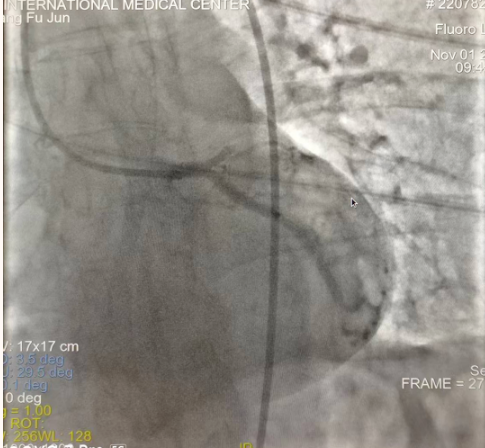

閉塞的血管再通時(shí)間取決于急救時(shí)長、轉(zhuǎn)運(yùn)時(shí)長和治療時(shí)長,在前兩方面,醫(yī)院已為患者爭(zhēng)取了最短時(shí)間?;颊呒覍龠h(yuǎn)在陜北,雖然已在趕來的路上,但最快抵達(dá)西安也要3小時(shí),在與患者家屬電話溝通同意急診手術(shù)后,醫(yī)療總值班代家屬簽字,康曉軍在請(qǐng)示心臟病醫(yī)院王海昌院長及心臟內(nèi)科CCU尚福軍主任后,積極進(jìn)行術(shù)前準(zhǔn)備。在沒有家屬陪同、沒有交費(fèi)、沒有辦入院手續(xù)的情況下,患者經(jīng)胸痛中心綠色通道被送往心臟冠脈介入手術(shù)室,打通了完全閉塞的心臟前降支近段血管。